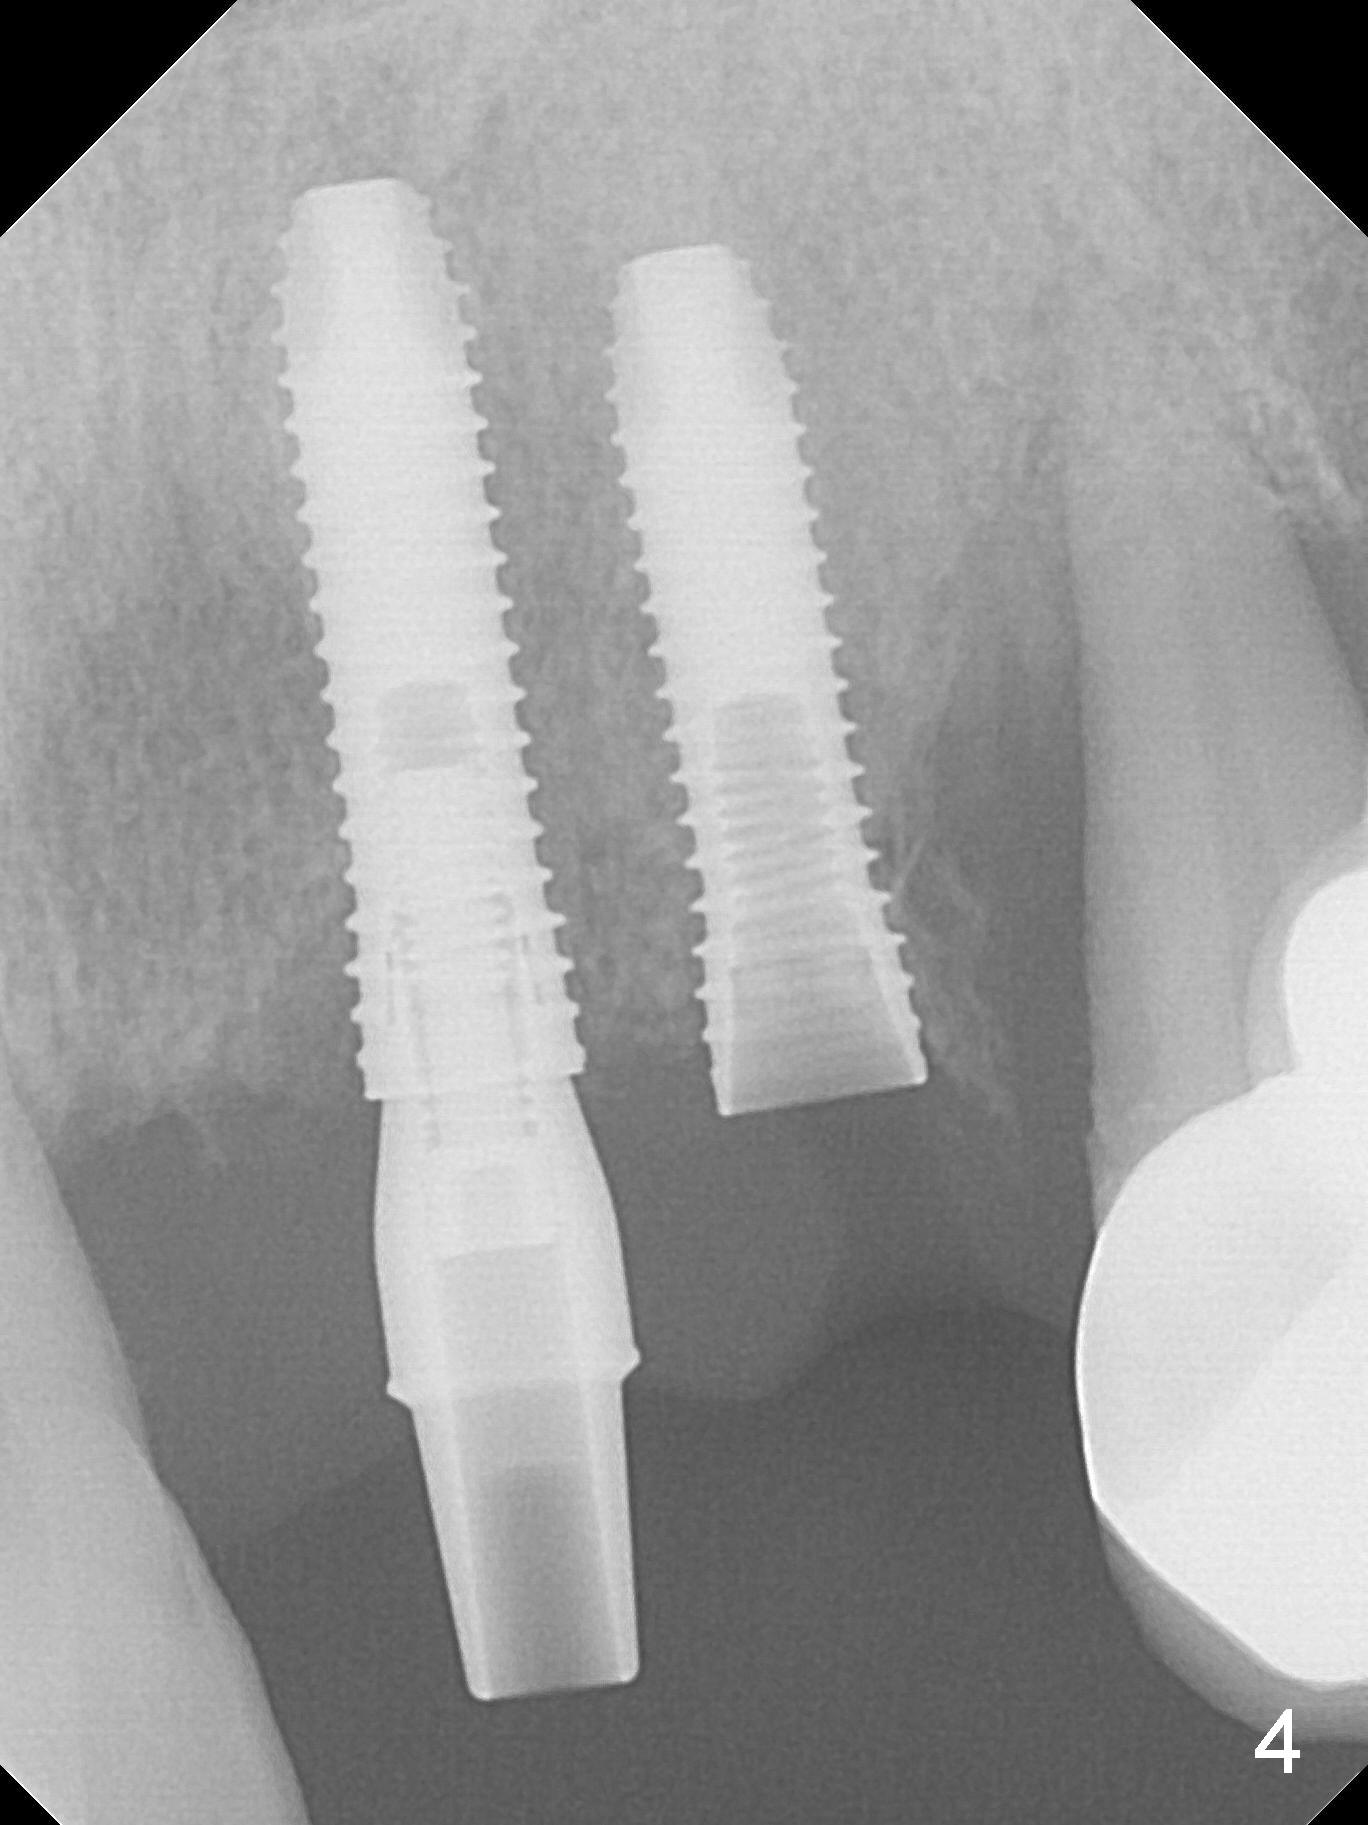

The dentition is poor except #6 and 8 (Fig.1). The gingiva is erythematous at #9-11 (Fig.2). The teeth #9 and 10 are extracted first; a 4x16 mm UF implant is placed at #9, while a 2 mm pilot drill is at the site of #10 (Fig.3). The implant at #9 is placed deeper with placement of 4.5x5.5(5) mm abutment; a 3.8x15 mm implant is placed at #10 initially (Fig.4). While the latter is placed deeper, a 4x16 mm implant is placed at #11 (Fig.5 after removal of #11-15 FPD (fixed partial denture)). In fact the trajectory at #11 is not difficult to be changed with 2 mm drill (Fig.6). After use of 3 mm drill, the implant is reinserted at #11 with ideal trajectory (Fig.7). After further seating of the implant at #11, graft is placed in the remaining sockets of #9-11 (Fig.8 *; later more graft is placed mesial to #11 implant (^)). Finally, a 4.5x7(5), 4.5x15° B (4) and 5.5x7(5) mm abutments are tightened and prepared (Fig.9) for splinted provisional at #9-10.